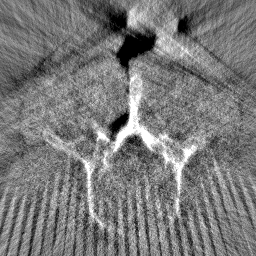

Disentanglement and explicit shape constraints. As shown in Fig. 4, we can see streak metal artifacts nearly everywhere in . M1 can roughly disentangle artifacts and anatomical information but strong vertical artifacts and strange air area appear in (see red arrows of M1 in Fig. 4). For the anatomical structure, M1 learns to segment vertebrae with fully supervised and applied on various CT images, but fails to suppress the false bony structure in and as may misclassify some metal artifacts as bone.

Implicit shape constraints. With , all segmentations are improved with higher Dices and smaller ASDs, see Table 1. As shown in Fig. 4, , and become similar but the high density bone is not correctly segmented in as it maybe treated as metal artifacts. Comparing between M2 and M1, the abnormal air region disappears but metal artifact reduction performance is still not satisfactory.

Anatomy-aware generation. With AADE layer in M3, , and are substantially improved as shown in Table 1. Note, is used as attention map, so we do not expect it to be identical to . In , metal artifacts are further suppressed comparing with M2. Thus, AADE is critical to our anatomy-aware artifact disentanglement framework. With the special structure, can be punished in the image translation and reconstruction processes and the other encoders and generators receive more guidance. However, as shown by blue arrows in Fig. 4, we observe a shadow of vertebra edge of appears in of M3 and the vertebra boundaries get smoothed out in . It may be because sharp edges are encoded as metal artifacts and forced to be added to by artifact consistency loss .

Removal of . To mitigate vertebrae shadows, we remove . The segmentation performance of most images in M4 gets improved because of better synthetic images. Overall, in M4 yields the best segmentation performance for CBCT images with an average Dice of 0.847 and an average ASD of 1.54 mm. For the synthetic images, M4 generates with the best quality and least metal artifacts among all the models. M4 also outputs without vertebra shadows. The results indicate our shape-aware network could preserve anatomical details and transfer the metal artifacts precisely without .